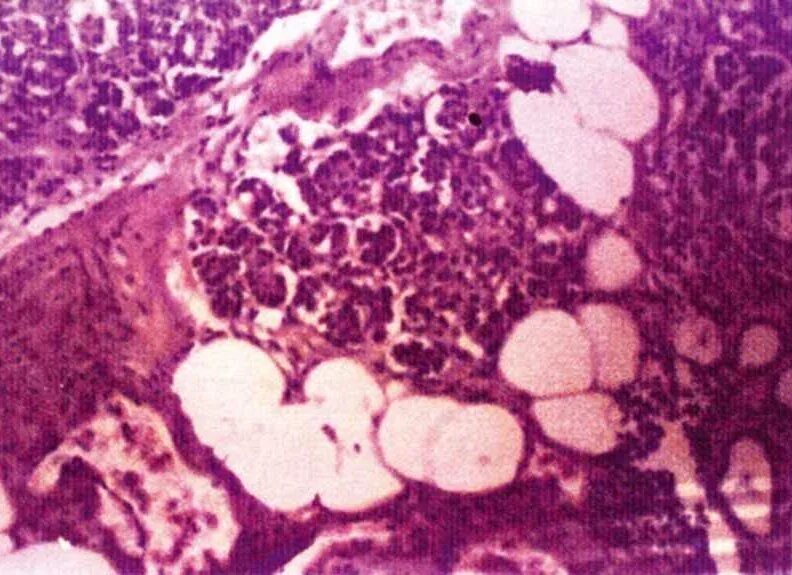

Липоматоз поджелудочной лечение лекарствами